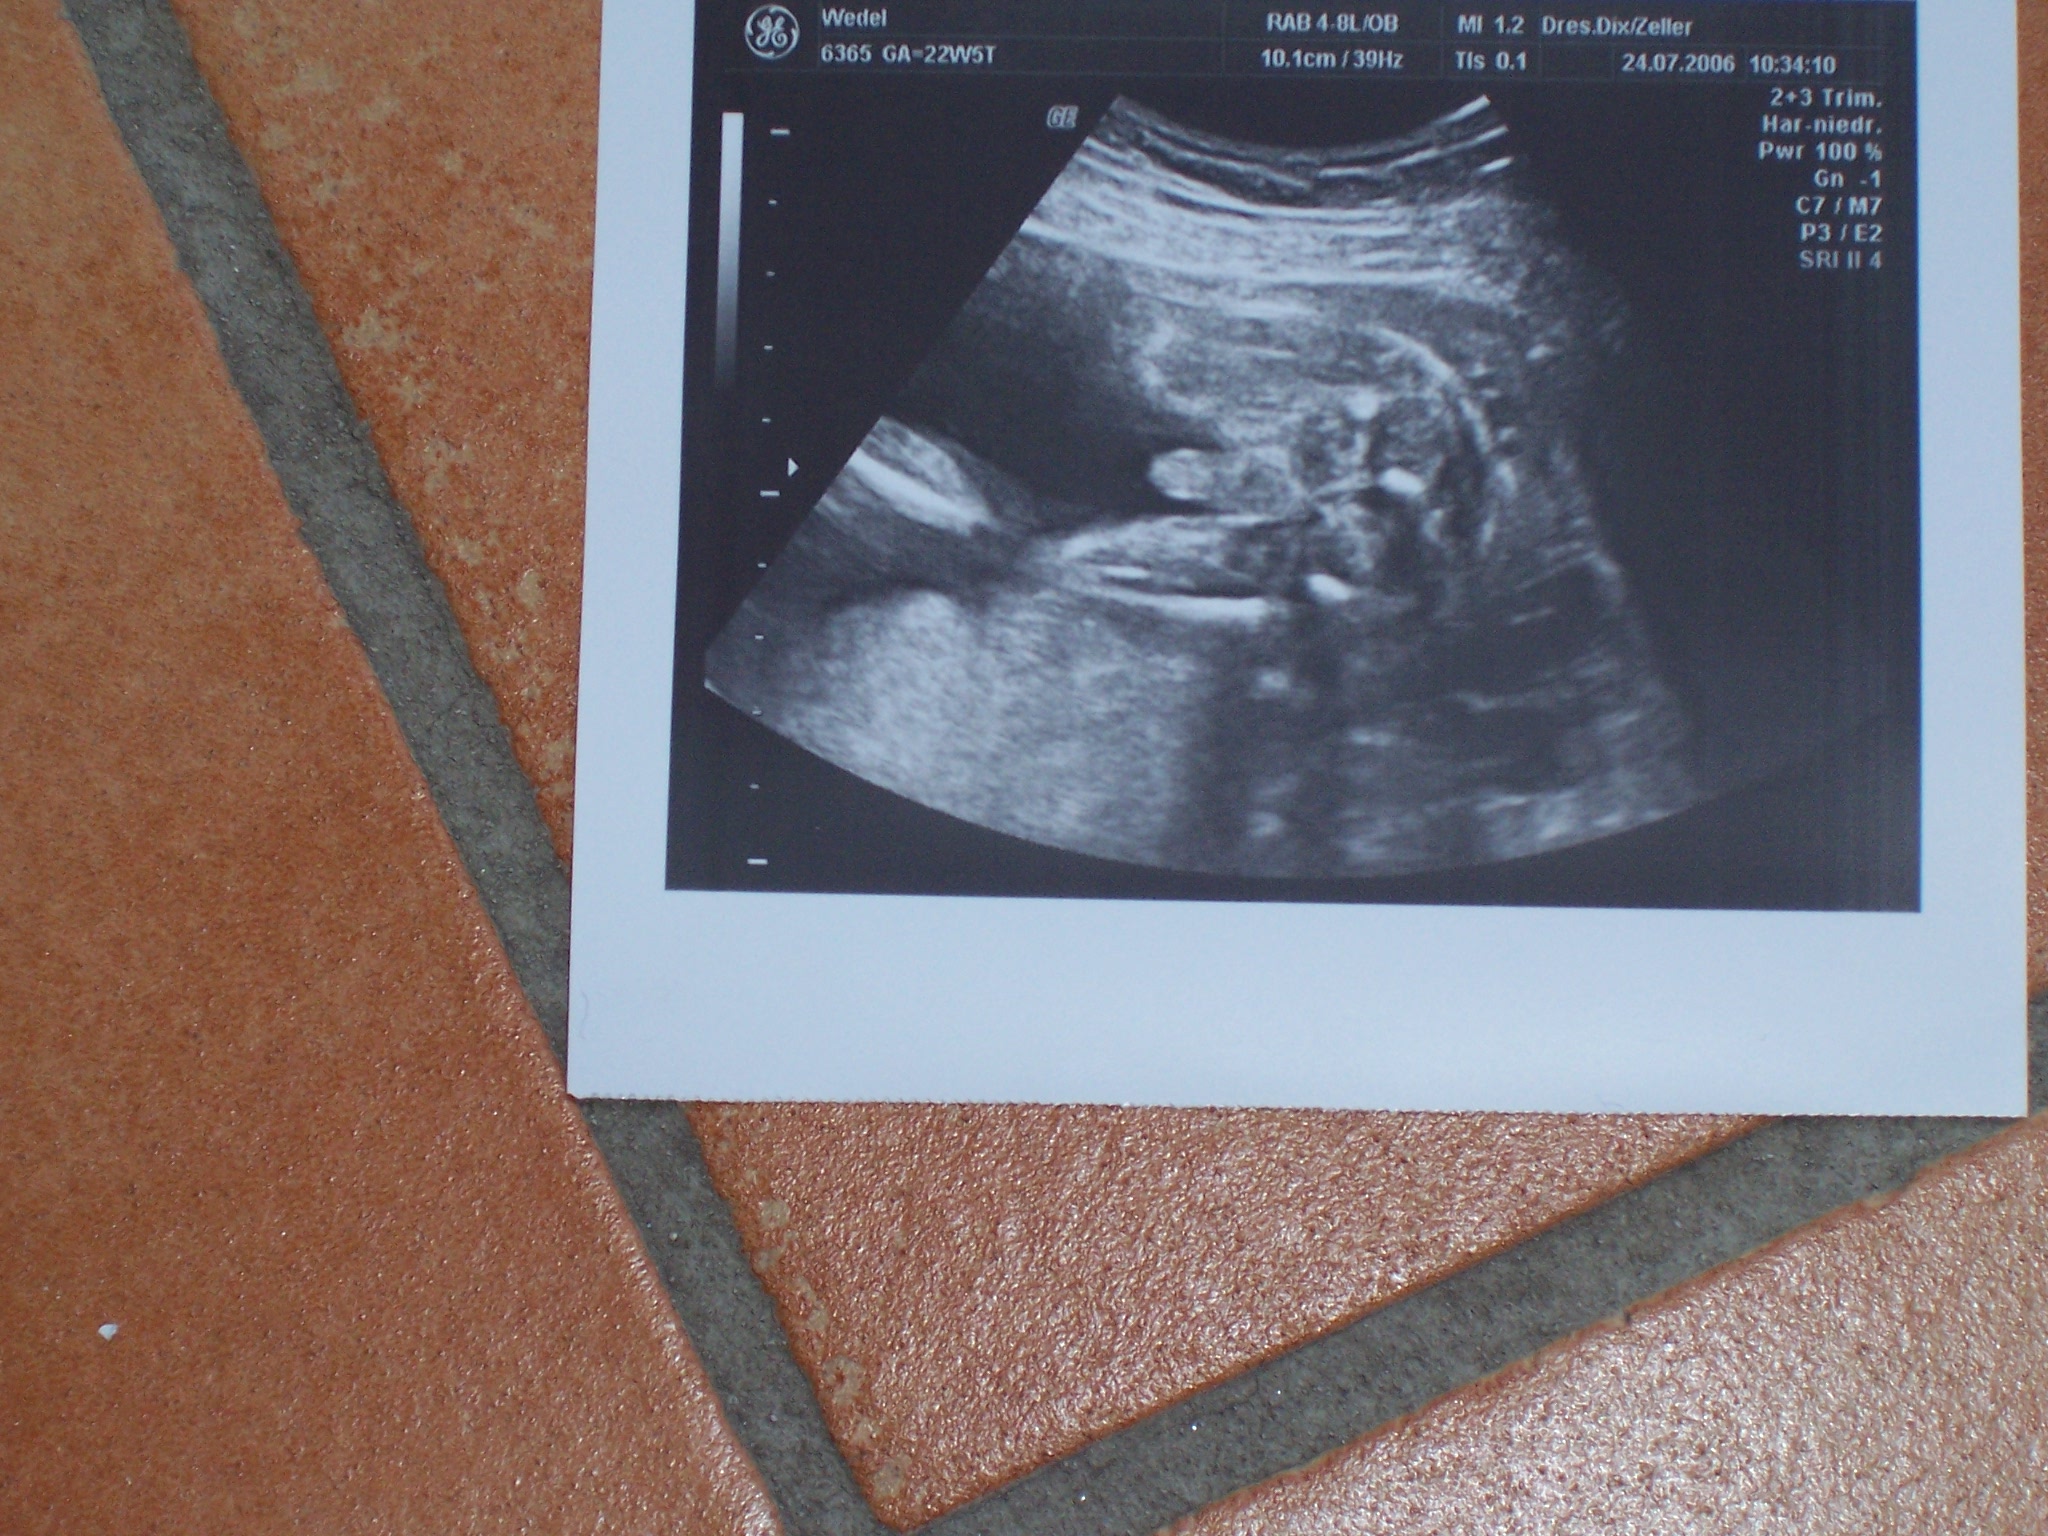

Wir hatten gestern wieder US. Die große Überraschung war, dass meine Ärztin jetzt einen 3 D US hat. Das war toll

Wir haben auch ein 100 % Outing bekommen. Es ist doch ein Junge

Ich stelle euch gleich noch Fotos ein. Auf dem einen ist der absolute Beweis drauf